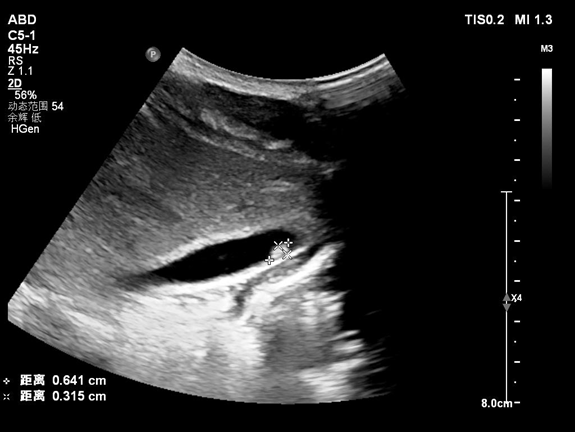

現有的證據都指向了寄生蟲,在醫生的建議下,小凱一家三口都做了寄生蟲相關檢查,結果顯示,三人血常規中嗜酸性粒細胞都異常升高!小凱還有肝功能異常,彩超顯示肝內有片狀低回聲區,肝門淋巴結腫,媽媽的大便中檢出肝吸蟲卵!